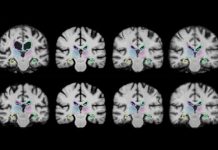

Tech: Faster analysis of medical images — (Report)

Medical image registration is a common technique that involves overlaying two images, such as magnetic resonance imaging (MRI) scans, to compare and analyze...